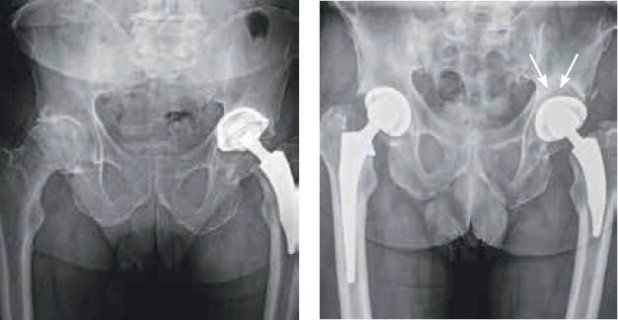

Bei einigen Patienten konnten wir im Rahmen einer beidseitigen Hüftoperation grosse Knochendefekte mit Eigenknochen von der Gegenseite rekonstruieren. Bei diesen Patienten wurde aufgrund einer Arthrose eine einseitige Hüfttotalprothese implantiert. Der dabei immer entnommene arthrotische Femurkopf wurde dann bei der Pfannenrevision auf der Gegenseite zum Füllen eines Knochendefekts verwendet. Eine minimal-invasive Technik am Patienten in Rückenlage ermöglicht die Durchführung beider Eingriffe während derselben Narkose («einzeitig») und ohne Umlagerung, was sich günstig auf die Rehabilitation auswirkt.

Zunächst wurde minimal-invasiv eine Hüft totalprothese rechts implantiert. Der entnommene Femurkopf diente danach auf der linken Seite dazu, den Knochendefekt hinter der Pfanne zu rekonstruieren.